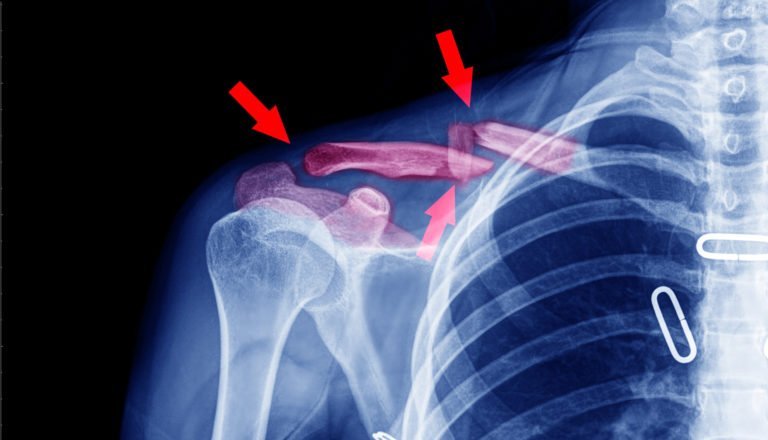

Why Are Broken Collarbones So Serious?

Collarbones play an important role in the human body. They stabilize the arm they are connected to and assist in your range of motion. As a result, you can’t move the arm connected to whichever collarbone you broke.

Unfortunately, collarbones are also relatively delicate as far as bones go. It doesn’t take much force to fracture one. Once that’s happened, both the broken collarbone and the connected arm typically must be immobilized while the fracture heals.